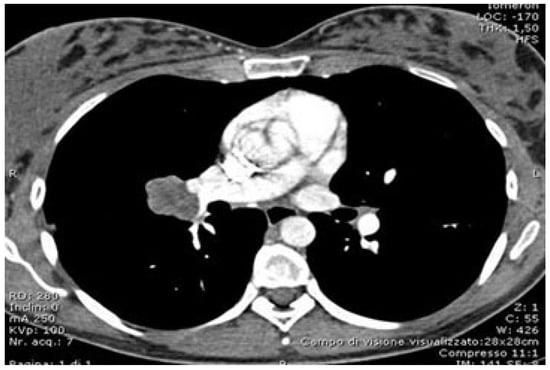

Figure 1. CT scan showing the target lesion.

In recent years, the use of a robotic platform has been implemented in a variety of resections: bronchoplasty, sleeve resections, pneumonectomies, and chest wall resections [40,41,42,43,44,45]. Various experiences have shown the feasibility of minimally invasive bronchoplasty and bronchial sleeve resections. Moreover, it is a fairly consolidated awareness that robotic surgery is a simpler technique compared to VATS. One of the reasons is the reduction in the VATS “fulcrum effect” owing to the presence of straight, non-articulated instruments, a better visualization, improved ergonomics, and a more precise tissue manipulation. A study published by Qiu in 2020 compared the perioperative outcomes of sleeve pulmonary lobectomy among all three techniques: robotic, open, and VATS. A higher mortality was observed among the VATS cases, while the robotic group registered a lower bleeding loss, early chest drain removal, and a shorter surgical time [42]. The advantage of robotic surgery in bronchoplasty or bronchial sleeve compared to VATS is an easier visualization of the bronchial stump and maneuverability of the needle holder with the EndoWrist instruments (Intuitive Surgical, Inc., Mountain View, CA, USA). Furthermore, the use of a self-locking wire allows for blocking the wire and keeping the suture tighter compared to the classic monofilament, especially in the case of anastomosis (Figure 1).

In the literature, there is still little data concerning robotic pneumonectomies. In 2021, Patton and colleagues described a series of 13 patients who underwent robotic pneumonectomy. Of these, 8 procedures were carried out with a minimally invasive approach, whereas 5 cases were converted to thoracotomy. The average hospital stay for robotic pneumonectomies was 4 days, while for converted cases it was 7 days. The duration of surgery was significantly longer in converted cases (226 min vs. 374). All conversions occurred for anatomical reasons, not because of hemorrhage [31]. In 2021, Scheinerman described an anterior approach to robotic pneumonectomy with the isolation of the inferior pulmonary vein followed by that of the superior pulmonary vein. In left pneumonectomies, it is necessary to perform an extensive lymphadenectomy in order to isolate the main bronchus at the origin and reduce to a minimum the length of the stump [43]. In a recent paper, Louie concluded that robotic pneumonectomy requires further development, particularly in terms of management of the pulmonary artery and of the evaluation of the bronchial stump length on the left. Finally, robotic pneumonectomy should be reserved for centers with considerable experience [44] (Figure 2).